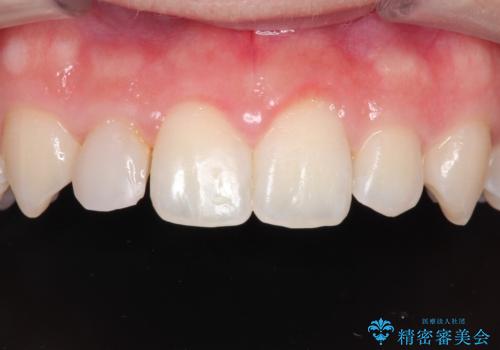

- 上の歯の隙間が気になるとのことで来院されました。

上顎の正中に隙間があり、右上の2番目の歯が通常の歯より小さい矮小歯でした。

正中の隙間をインビザライン矯正で閉鎖して、右上の2番目の歯にはセラミックを装着する計画としました。

矯正治療とセラミック治療を組み合わせることにより、審美的により良い結果を得ることができました。